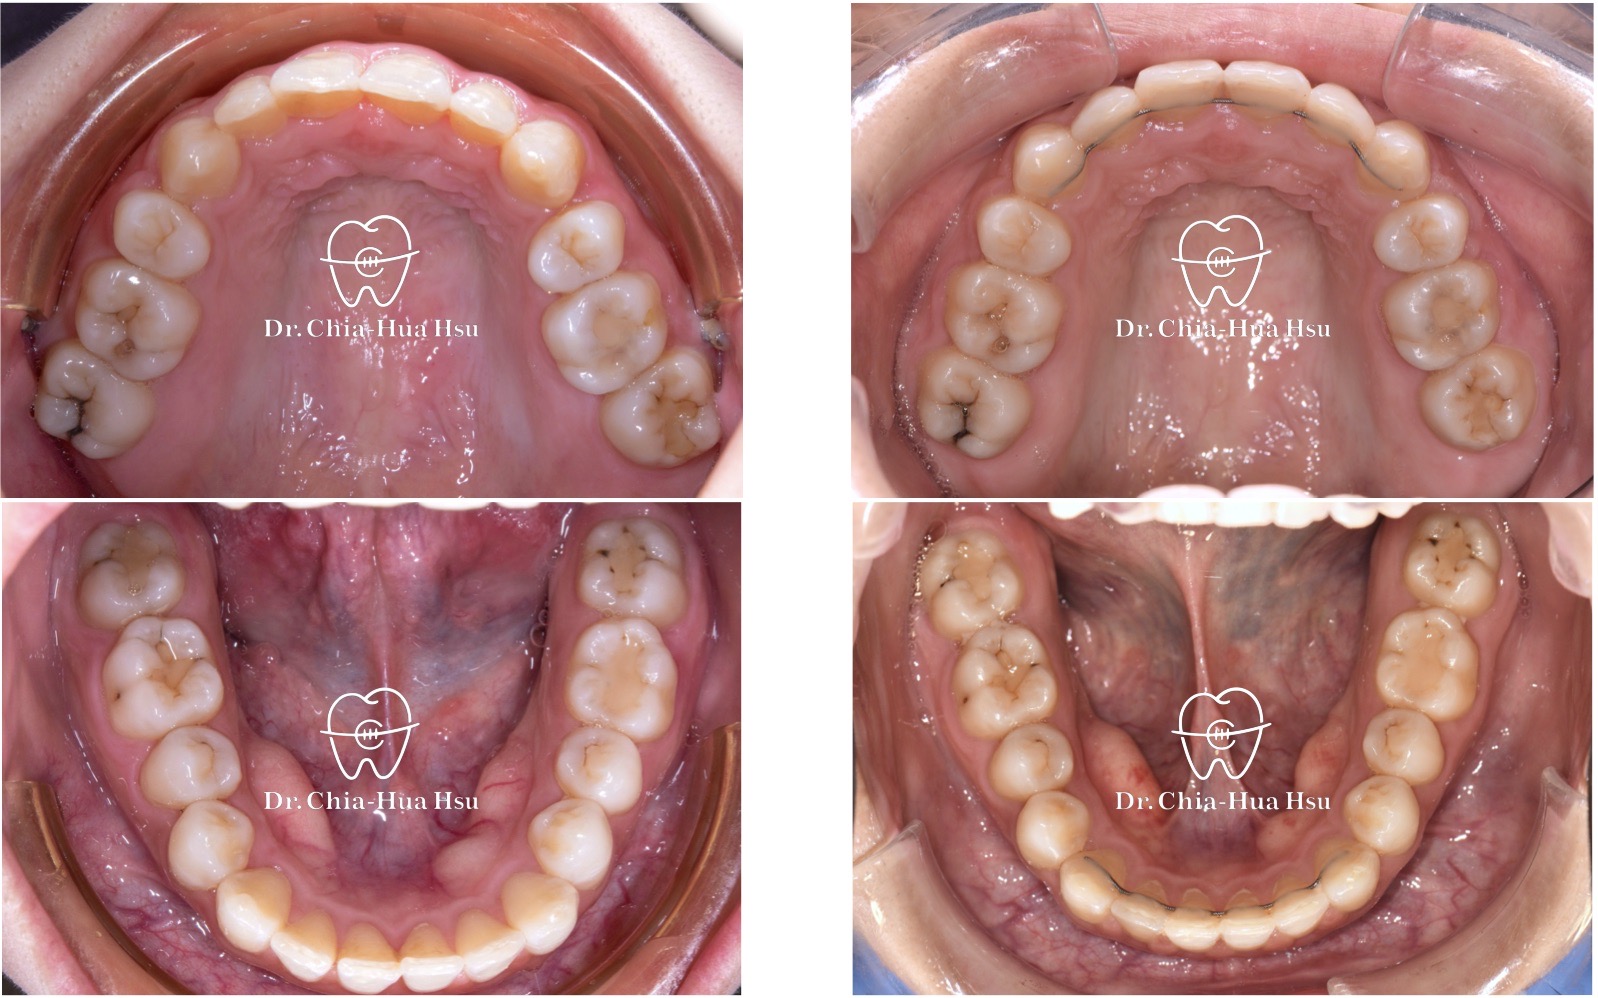

- 治療方式:使用傳統金屬矯正器,使用原有骨釘將上顎牙齒前移,迅速將療程結束。

- 治療時間:1 年 3 個月。

- 治療結果:齒列排齊,笑容更燦爛。

治療後